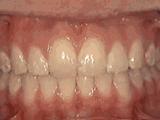

4、牙列拥挤,前牙没有咬合,上下牙齿中线不对称,牙弓狭窄,上颌“*牙虎**”异位生长,经专业评估没有拔牙,经过矫正后的牙齿是这样的~